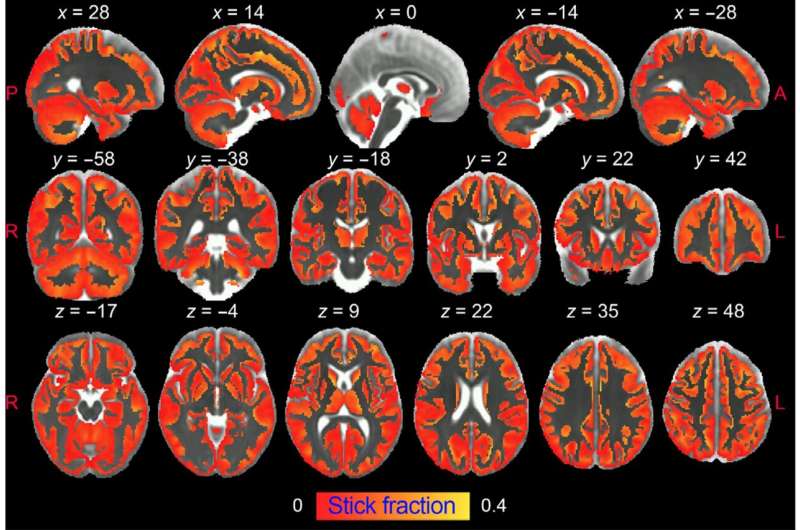

A new adaptive brain modeling framework offers fresh hope for objective diagnosis of neuropsychiatric disorders, which currently lack reliable neuroimaging biomarkers.